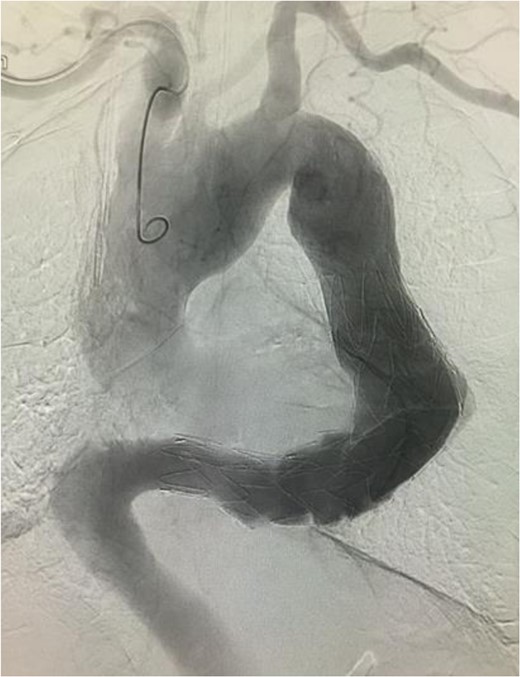

A stiff sheath (Destination®, 6 Fr 90 cm, Terumo, Tokyo) was introduced from the left side. The sheath was placed beyond the aneurysm. Lunderquist® guide wire was introduced through the sheath. The aortic angulation was straightened and the most severe angulation below the aneurysm was reduced (Fig. 2).

(a) A sheath was introduced and the angulation was slightly reduced. (b) A guide wire was introduced through the sheath. The angulation was further reduced by this procedure. In addition, the angulation of the wire (black arrow), which was used to introduce the stent graft main body, was reduced. Thus, the wire was advanced through the aorta where angulation was small.

The stent graft (Relay Plus® 38 × 34 × 200 mm, Bolton medical, Barcelona) was introduced through the right common femoral artery. When it reached the distal site of the thoracoabdominal aorta where the angulation was the most severe, the outer hard sheath was left there while the inner flexible sheath was advanced. The flexible sheath was successfully introduced to the proximal site of the thoracoabdominal aorta beyond the angulation (Fig. 3). The stent graft was placed and we confirmed that no endoleak existed (Fig. 4).

Intraoperative arteriogram. (a) The hard sheath was left at the distal site of the angulated part and the flexible sheath was advanced. The angulation was sufficiently reduced by additionally introducing delivery devices for the stent graft (sheath and guide wire). Thus, the stent graft was introduced to the proximal side of the angulated part beyond the aneurysm. Compared to the preoperative contrast CT coronal section image (b) a reduction in the angulation of the proximal aneurysm was observed.